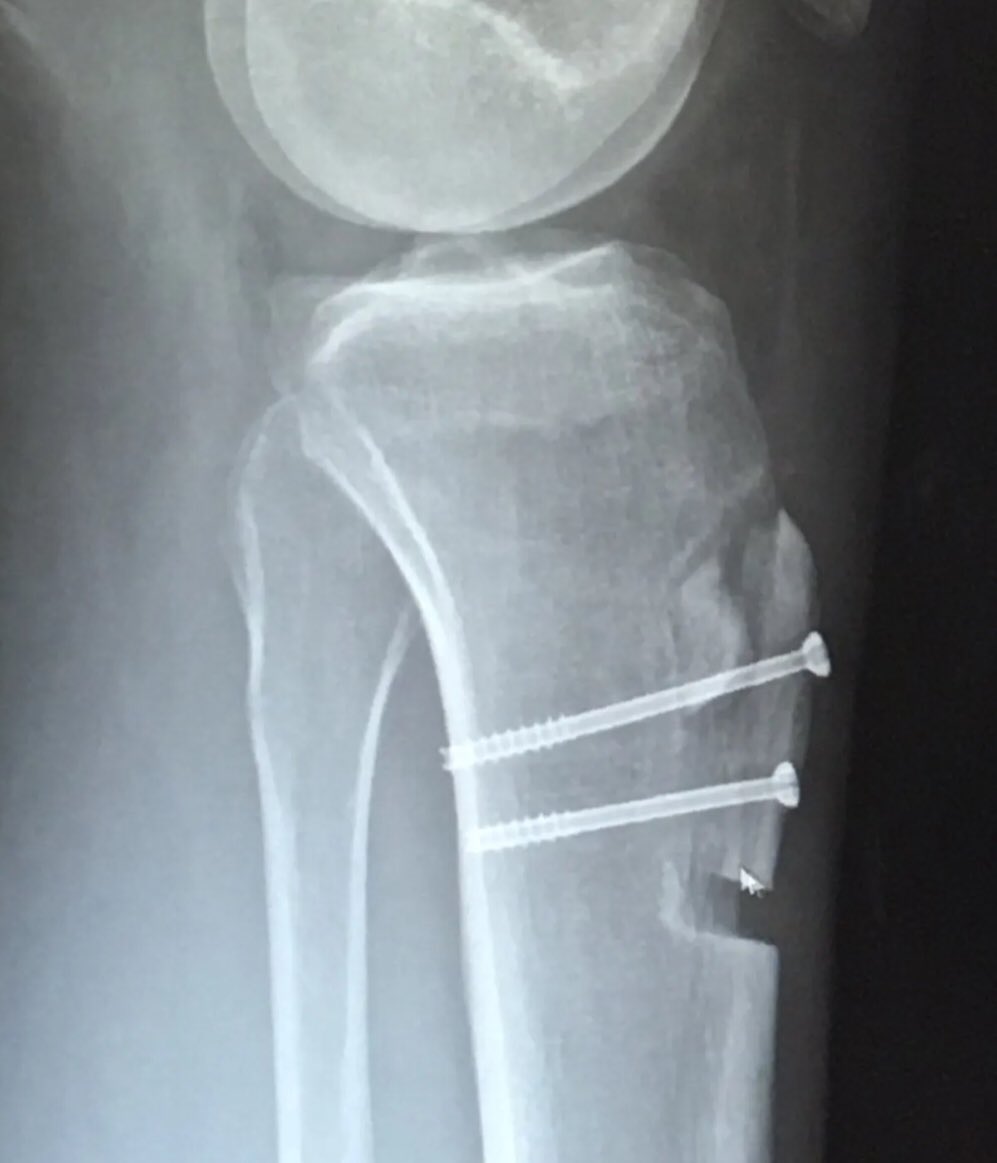

Both legs have had two surgeries to stop dislocations